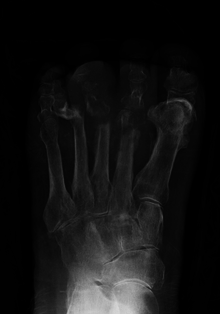

| Osteomyelitis of the 1st toe | |

Radiographs and CT are the initial method of diagnosis, but are not sensitive and only moderately specific for the diagnosis. They can show the cortical destruction of advanced osteomyelitis, but can miss nascent or indolent diagnoses.[12]

Diagnosis of osteomyelitis is often based on radiologic results showing a lytic center with a ring of sclerosis.[1] Culture of material taken from a bone biopsy is needed to identify the specific pathogen;[15] alternative sampling methods such as needle puncture or surface swabs are easier to perform, but do not produce reliable results.[16][17]